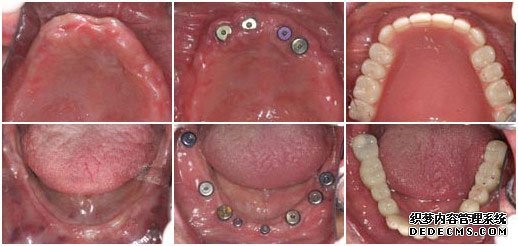

种植牙前                             植入种植体后                   套上烤瓷牙冠完成手术

患者:王老伯

年龄:61岁

职业:退休

牙症:全口牙缺失

检查:全口牙齿缺失,无能明显依托的牙根,X片显示根尖无异常

美牙方案:通过口腔数码内窥镜、口腔全景机及微创无痛设备,精密观测口腔内的状况,运用先进的瑞士ITI种植牙技术进行种植。

美牙后:全口牙修复成功,恢复了咀嚼功能,饮食和说话都能自如。

美牙技术:韩国登腾Dentium

美牙时间:6个月

王老伯来武汉爱齿尔口腔就诊的时候,情况非常糟糕,在医生的检查下,发现他口腔内的牙齿全部缺失,并没有可持久依托的牙根,面对这一情况,医生只有建议王老伯做种植牙。虽说种植牙的治疗时间较长,但是对于王老伯这样的牙齿状况,种植牙是一种十分理想的选择。

由于王老伯今年已经61岁,所以在植入种植体后的恢复时间比一般人要常一些,花了将近5个月的时间才长好,但这并不影响种植牙的效果。最后在套烤瓷牙冠的时候,王老伯的家人也感到十分惊异,因为种出来的牙齿不但美观漂亮,甚至比王老伯之前的真牙还要逼真,一下子王老伯的牙齿看起来仿佛只有20多岁。而最最高兴的还是王老伯,他说:“我以前戴的全口活动假牙,吃东西不方便,连老伴弄的饭菜也都不想吃,可这次种牙太成功了,真是那句老话:‘牙好,胃口就好啊!’,太感谢你们了”